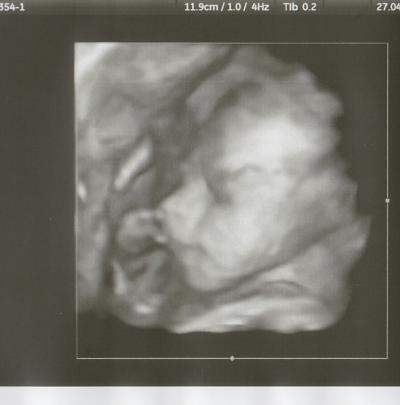

Huhu Hatte gestern meinen Zuckertest und mein erstes CTG Und vaginaluntersuchung bei der Ärztin, aaaallllles i.O. !!! Da hab ich mich sehr gefreut. Und dann durfte ich ganz unverhofft noch auf unsere kleine Motte schauen, weil die Ärztin gucken wollte wegen der Lage, ich war hin und weg Sie liegt mit dem Popo nach unten Muß man sich da jetzt schon Gedanken machen?, habe es ja schon mehrmals von Euch auch gelesen! Unsicher LG BELLA ich hänge mal das Bildchen an

Bild zu Gestern FA-Termin :-) - Forum für August - Mamis